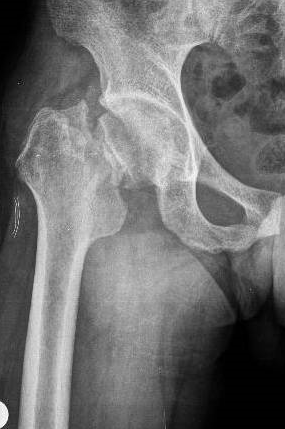

FEMUR BOYUN KIRIKLARI

Doktor Mehmet Subaşı

Tüm kırıkların yaklaşık %1 ini oluştururlar. Sıklıkla 60 yaş ü...